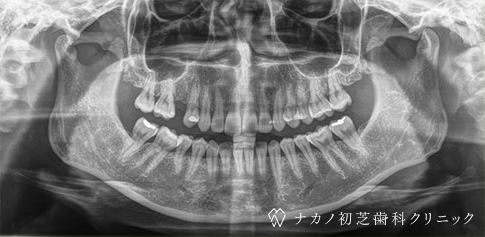

インプラント・1本 (30代女性)

-

BEFORE

AFTER

年齢 30代女性

治療内容 インプラント治療1本

インプラント治療とは、歯を抜いた所にチタン製の人工歯根を埋入し、その上に歯を入れる方法です。費用 1本 400,000円(税込 440,000円)

リスク・副作用

腫れ・疼痛・違和感を感じるなどの症状を生じることがあります。